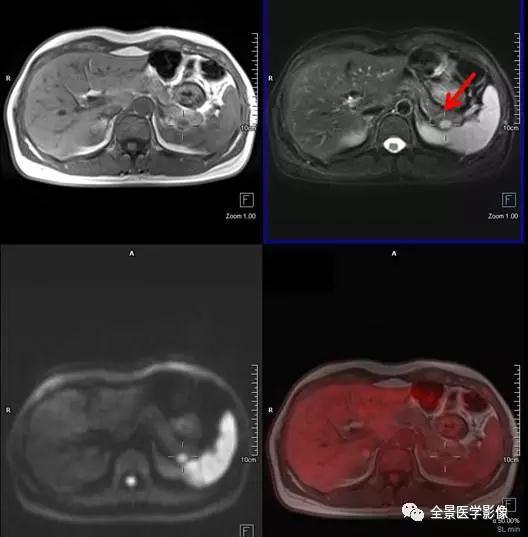

PET/MRI

脾脏

血管瘤

◆ 案例:青年男性,无不适主诉。脾脏可见一类圆形异常信号灶,长径约 1.0 cm,FDG 无代谢,考虑为脾脏血管瘤。

点评:

脾脏血管瘤属于脾脏良性肿瘤,发生基础与肝脏血管瘤相似,生长缓慢,通常都是偶然发现,此例血管瘤仅 1.0 cm,不需要外科处理,B 超定期复查即可。

淋巴管瘤

◆ 案例:中年男性,肝转移瘤患者。脾脏可见 1 枚异常信号灶,大小约 2.8 cm×3.6 cm,FDG 无代谢,考虑为良性病变,脾脏淋巴管瘤。

脾脏淋巴管瘤也属于脾脏良性肿瘤,系由囊性扩张的淋巴管构成,生长缓慢,病灶小,无临床症状者,不需要外科处理,B 超定期复查。此例病灶 FDG 无代谢,PET/MR 帮助排除脾脏转移。